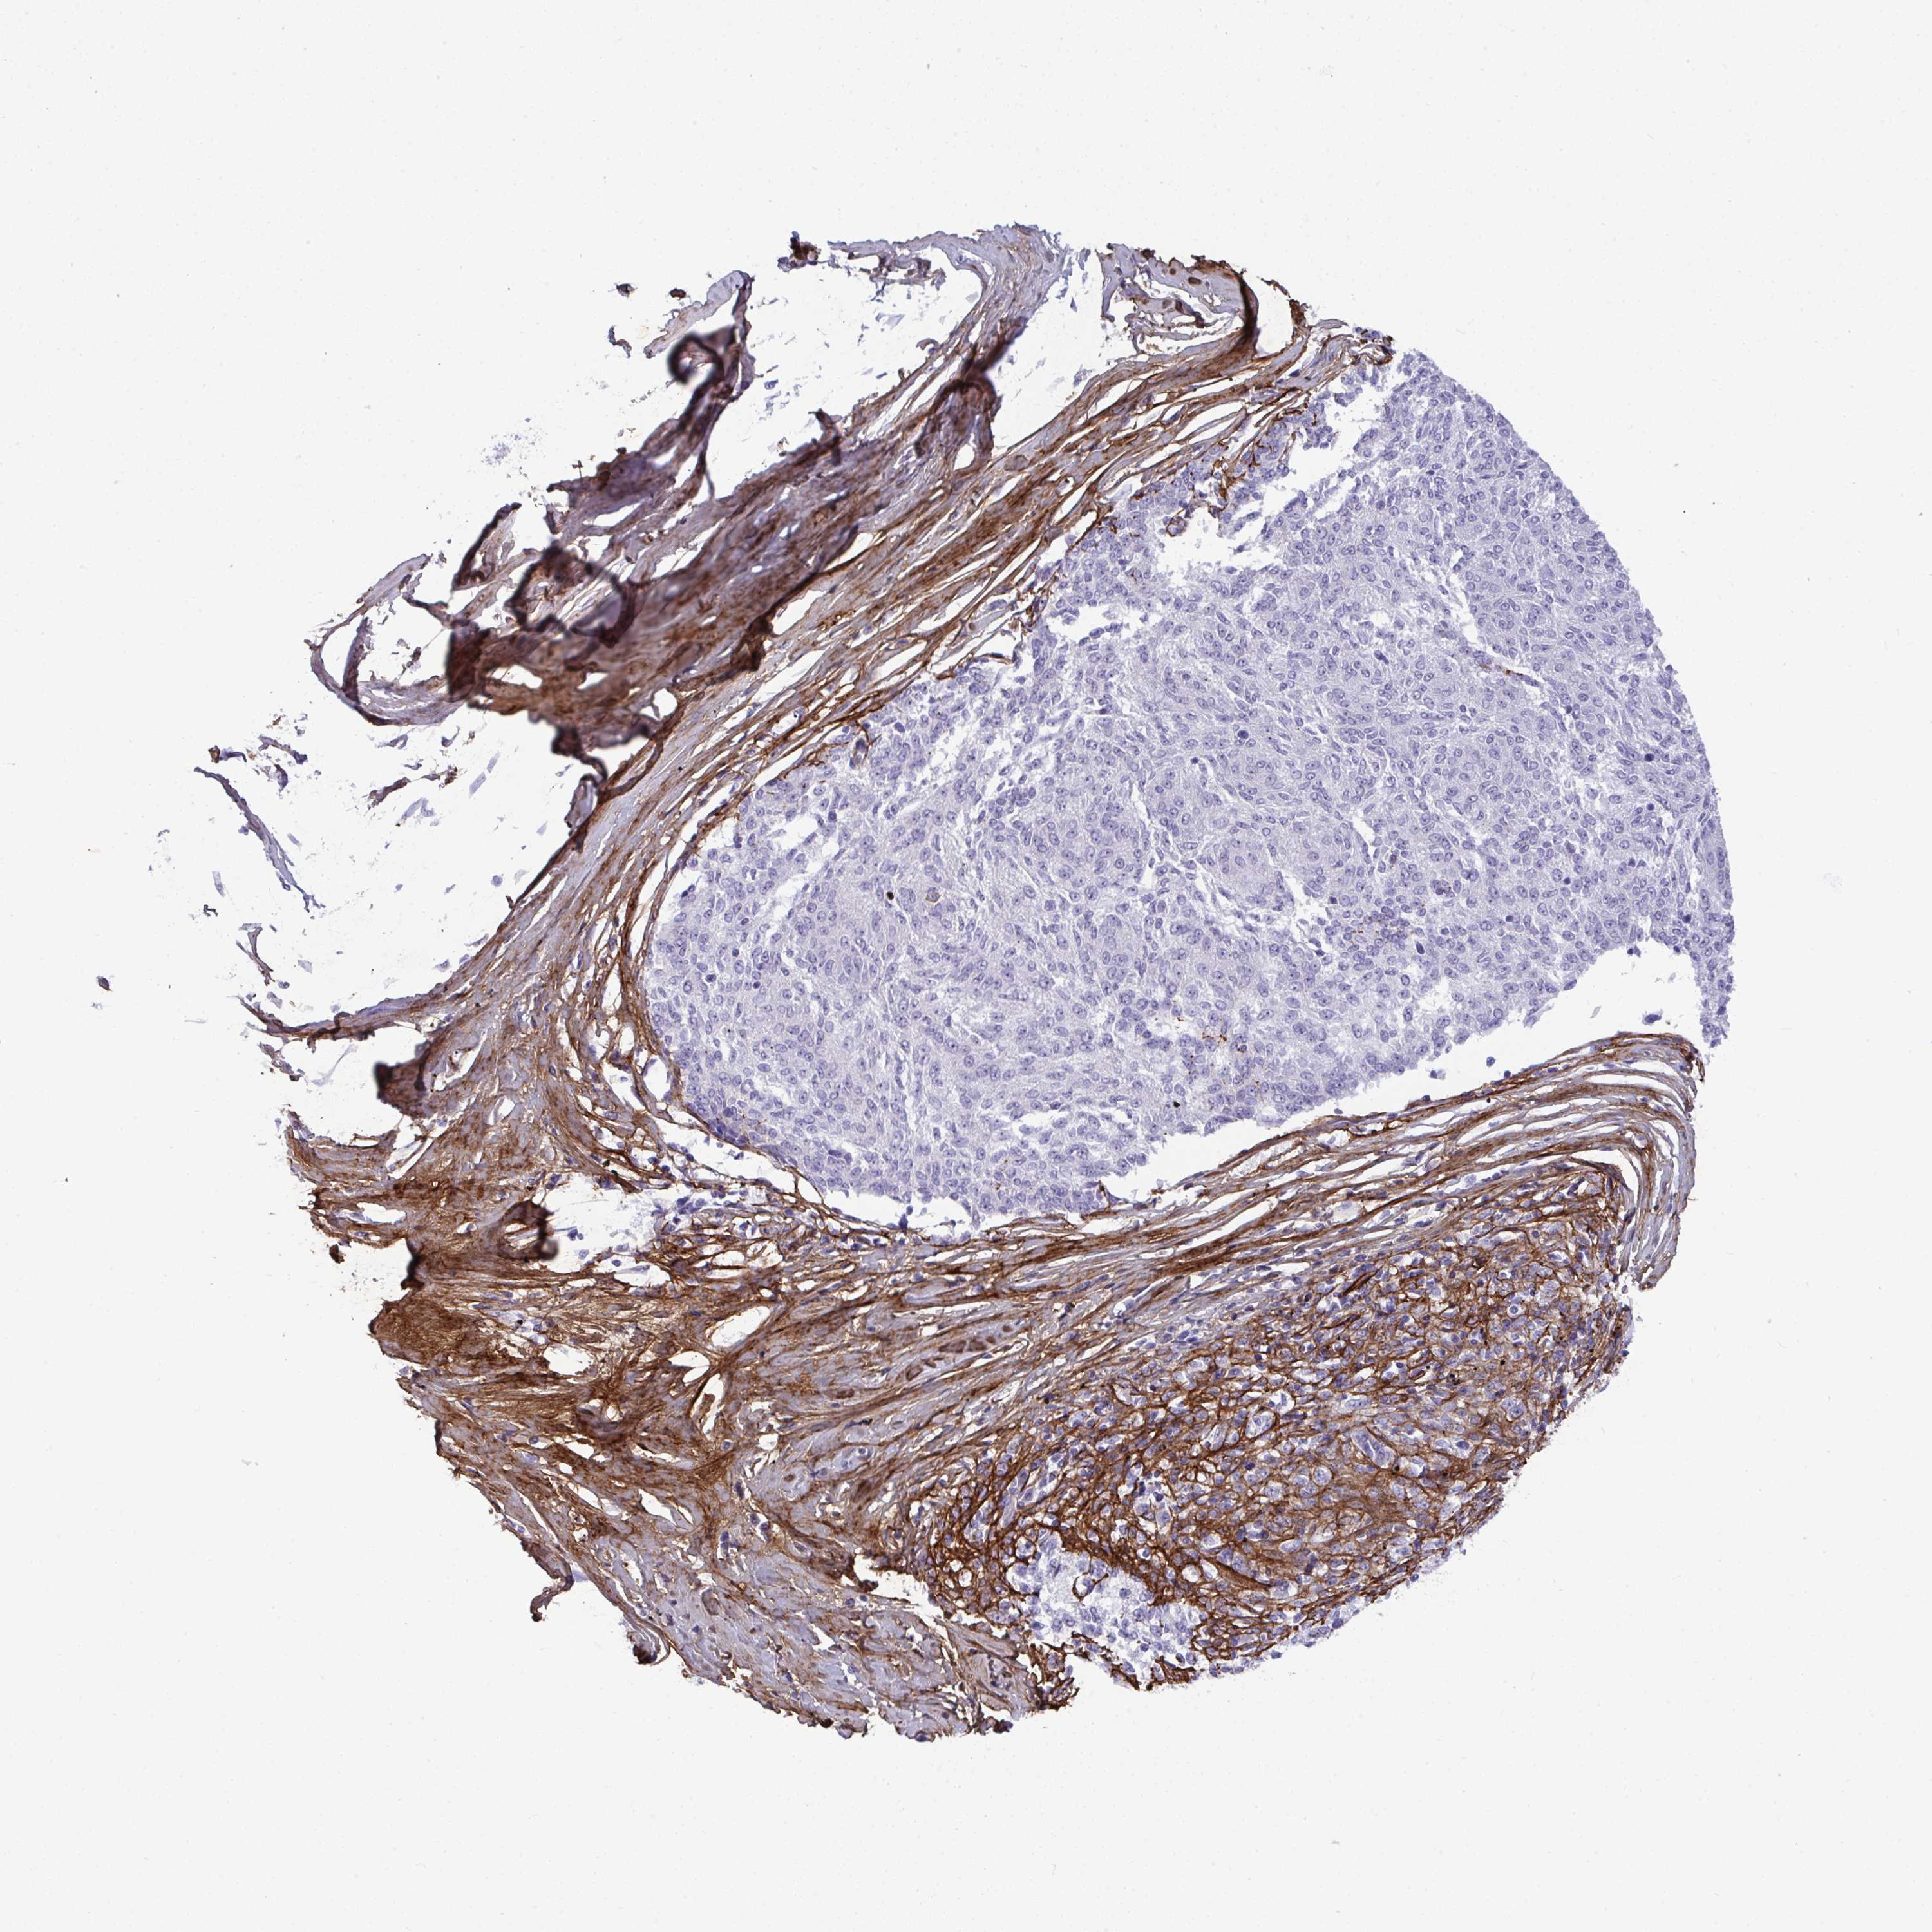

MELANOMA - Protein expressioni

A mouse-over function shows sample information and annotation data. Click on an image to view it in a full screen mode. Samples can be filtered based on level of antibody staining by selecting one or several of the following categories: high, medium, low and not detected. The assay and annotation is described here.

Note that samples used for immunohistochemistry by the Human Protein Atlas do not correspond to samples in the TCGA dataset.

Antibody stainingi

Antibody staining in the annotated cell types in the current human tissue is reported as not detected, low, medium, or high, based on conventional immunohistochemistry profiling in selected tissues. This score is based on the combination of the staining intensity and fraction of stained cells.

Each image is clickable and will lead to virtual microscopy that enables deeper exploration of all samples and also displays staining intensity scores, fraction scores and subcellular localization as well as patient and tissue information for each sample.

Antibody HPA058975

Malignant melanoma, Metastatic site

Malignant melanoma, NOS